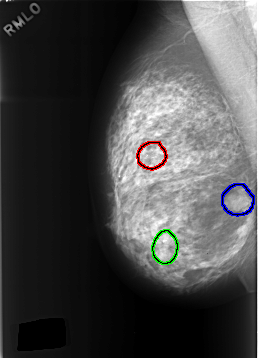

C_0307_1.RIGHT_MLO

FILE: C_0307_1.RIGHT_MLO.OVERLAY

TOTAL_ABNORMALITIES 3

ABNORMALITY 1

LESION_TYPE CALCIFICATION TYPE PLEOMORPHIC DISTRIBUTION CLUSTERED

ASSESSMENT 4

SUBTLETY 5

PATHOLOGY BENIGN

TOTAL_OUTLINES 1

ABNORMALITY 2

LESION_TYPE MASS SHAPE LOBULATED MARGINS CIRCUMSCRIBED

SUBTLETY 4

ABNORMALITY 3

ASSESSMENT 3